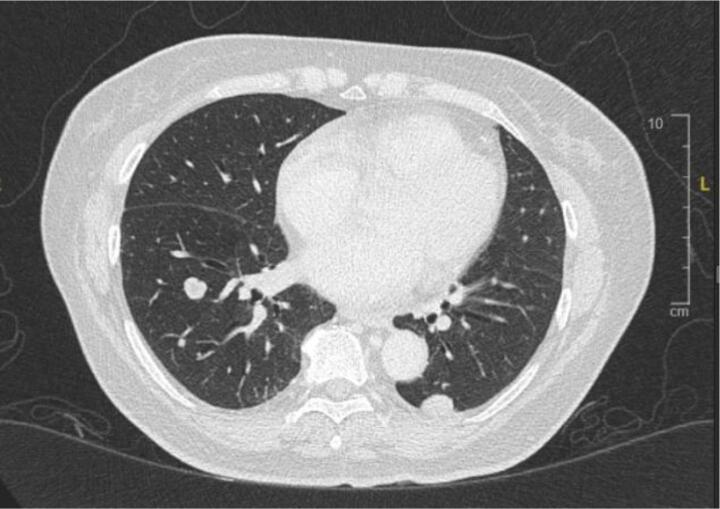

A 68-year-old Chinese woman was diagnosed with Stage IVB ULMS (spindle type) with lung metastasis in January 2021. Initial computed tomography (CT) revealed a uterine mass measuring 7.5 x 6.3x 5 cm (Fig. 2A), and multiple lung metastases (Fig. 2B). She underwent total abdominal hysterectomy with bilateral salpingo-oophorectomy (TAHBSO) and omentectomy in January 2021. Histopathological report revealed the tumour to be a malignant uterine tumour involving the myometrium, consisting of predominantly malignant spindle cells. Immunohistochemistry (IHC) report confirmed a profile consistent with ULMS. Estrogen Receptor/Progesterone Receptor negative. The patient was started on first line palliative chemotherapy: Gemcitabine and Docetaxel. She completed 6 cycles of this regimen in July 2021. CT reassessment at this point showed stable lung lesions (Fig. 2C). Following a one-month treatment break, CT imaging revealed an increase in size of the lung lesions, with no new lesions. The patient was then started on Pazopanib 800 mg OD. This was stopped after 3 months, due to treatment toxicity - Hand-Foot-Syndrome (HFS), associated with transaminitis and proteinuria. The patient was then started on Eribulin as third line treatment. She remained on this for 4 months until June 2022. CT imaging revealed disease progression, with new enhancing lesions suggestive of right-sided abdominopelvic recurrence and worsening lung and pleural base metastases (largest measuring 3.3x5.2x7.7 cm, previously 1.9x2.5x2.7 cm). The patient’s regimen was then changed to Doxorubicin and Cyclophosphamide. Although there is no universally accepted sequence of palliative chemotherapeutic agents, doxorubicin with cyclophosphamide is often attempted as first or second-line treatment. This was avoided in an early-line setting in this case to minimise the risk of cardiac toxicity. After 4 cycles of this regimen in September 2022, CT revealed further disease progression with increasing abdominopelvic enhancing recurrence, worsening lung and pleural-based metastases and liver metastases (Fig. 2D).

Fig. 2B.

Initial lung lesions pre-chemotherapy.

Fig. 2C.

Lung lesions post Gemcitabine.

In view of PD-L1 status of the tumour, she was started on immune checkpoint blockade. The decision was made to start on combination of pembrolizumab 200 mg, 4 weekly and temozolomide 300 mg D1-5, 4 weekly. CT after completion of cycle 4 revealed a reduction in right abdominopelvic mass size (3.4x2.2x2.4 cm, previously 7.2x5.2x5.6 cm), lung and pleural-based metastases (1.3x3.6x3.1 cm, previously 3.3x6.0x7.7 cm)(Fig. 2E). She was continued on the current regimen and is now on cycle 7. Patient has tolerated this regimen well throughout all cycles with minimal toxicity (Fig. 1).

Fig. 2E.

Response post Pembrolizumab + Temozolomide.